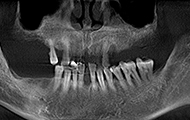

缺了8颗牙,名副其实的“缺牙一颗带坏全口”,在检查后,我右边的第一缺牙已经有严重的骨萎缩了,是“纸片骨”,种牙难度很大,我从湖南跑到深圳,可以说一路都在对比医院和方案。

过去十天了,今天去拆线,然后歇上一段时间,我的手术创口比较多,难免要缝合。种植体重新拍摄了CT,植入良好,医生今天给我检查,种植牙术后并没有肿胀,恢复的还算不错,看来我老骥伏枥,体质还不错,也感谢医生种牙技术的高超,种植体都是微创的手术,种植牙的创口减小了,种植牙术后就更容易恢复了。